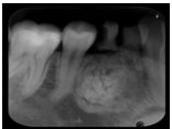

74.下圖白色箭頭所指之X光影像,下列何種病變最有可能?

(A)Squamous cell carcinoma (B)Cementifying fibroma (C)Buccal bifurcation cyst (D)Dentigerous cyst